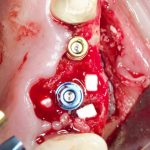

Простой синуслифтинг. Часть I.